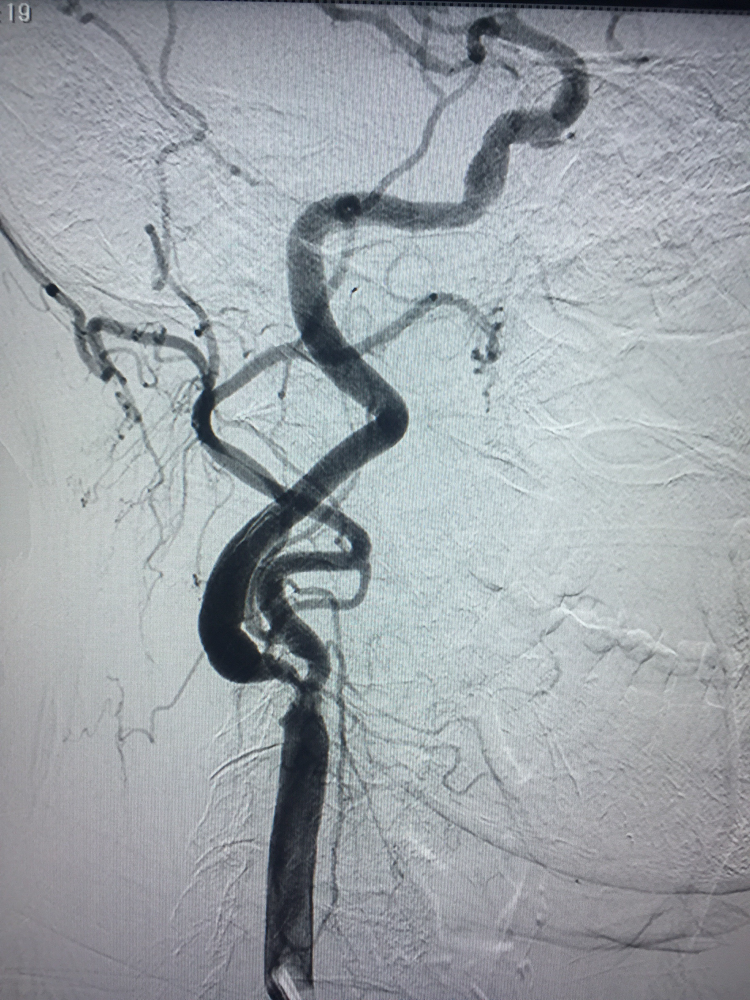

Hình ảnh Động mạch cảnh phải trước Nong và và đặt stent: hẹp khít đoạn gốc RICA.